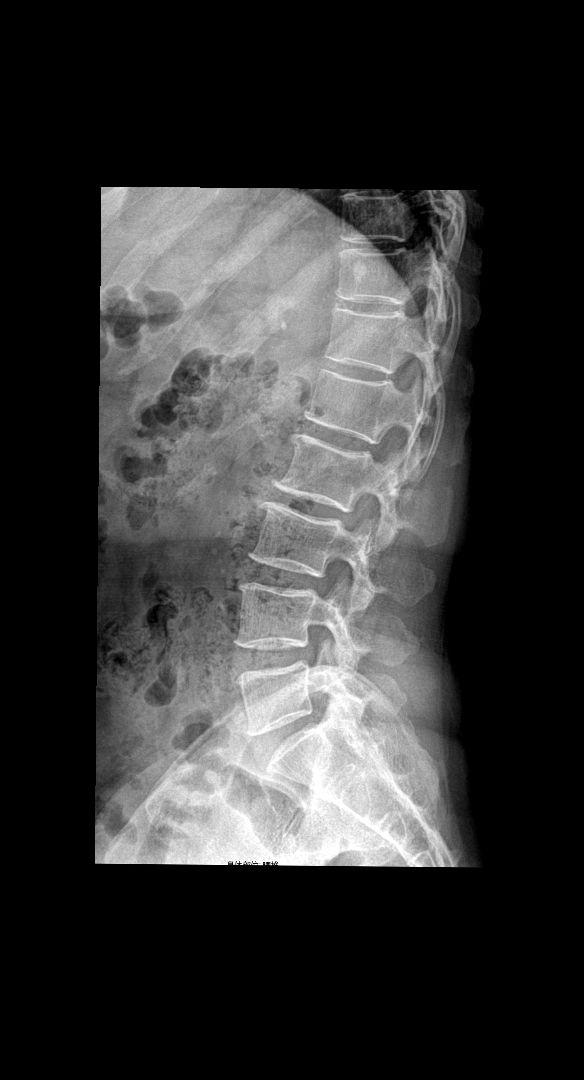

腰椎正侧位